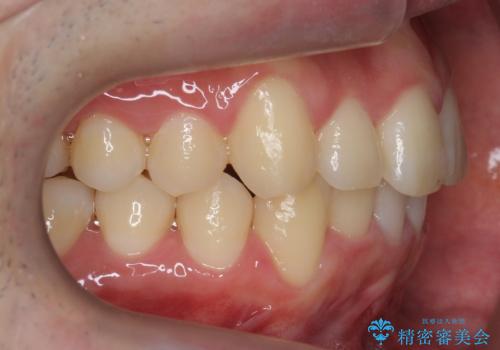

前歯のがたつき マウスピース矯正で 非抜歯で奥歯を後ろに下げる治療

- 前歯のがたつきを主訴に来院。

歯を抜かずに、奥歯を後ろに下げ、歯の両側をわずかに削って並べました。

歯のがたつきがなくなると、歯ブラシがしやすくなり、茶色いステインも付きにくくなります。